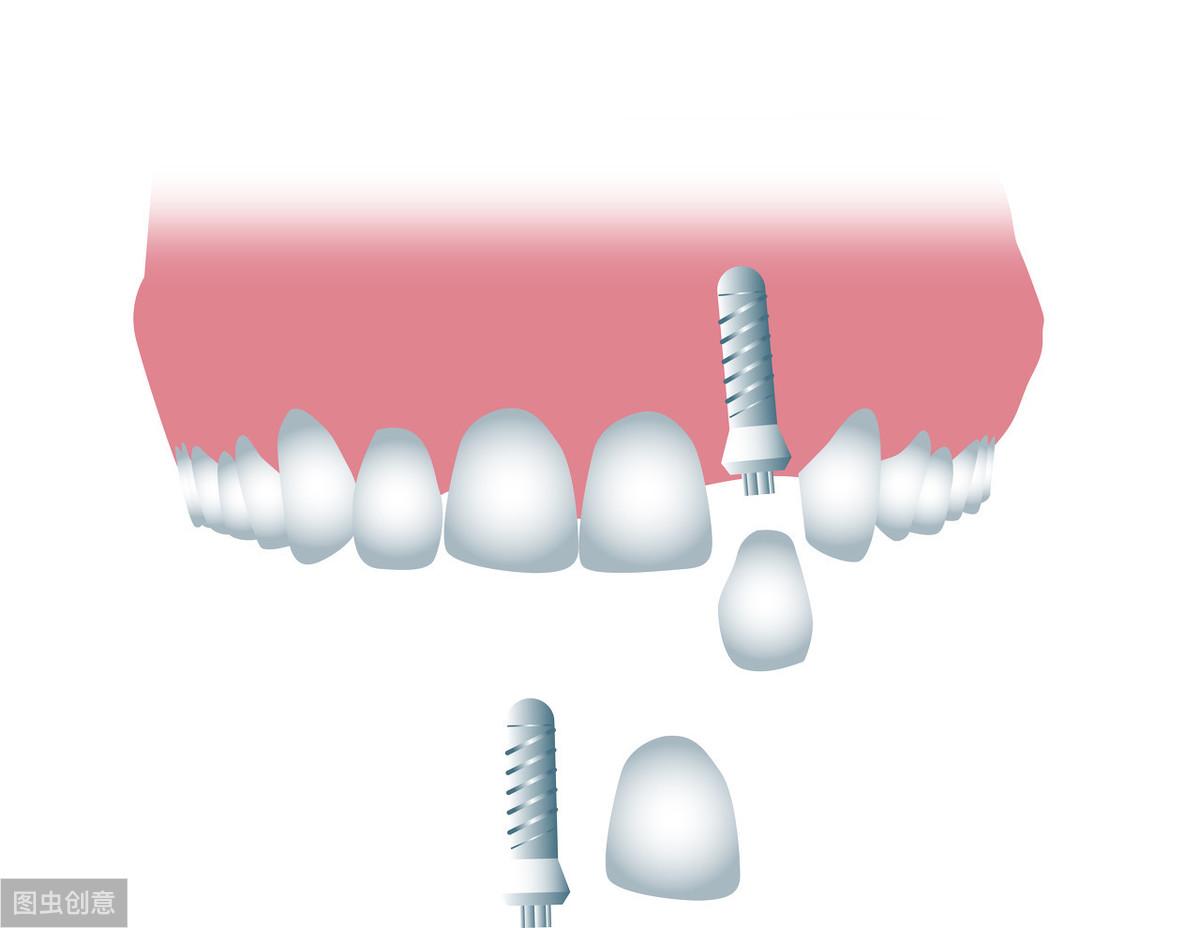

牙齒種植術(shù)是目前好的缺失牙齒修復(fù)技術(shù)之一,因?yàn)樗姆N植技術(shù)是通過(guò)手術(shù)將種植體植入到牙槽骨里,獲得了骨組織的固位支持,所以種植牙齒的穩(wěn)定性、性和使用年限都高,因此,種植牙從發(fā)展到現(xiàn)在也獲得了醫(yī)學(xué)界專家廣泛的認(rèn)可和大量有需要患者的喜愛。

也正是因?yàn)樾枰ㄟ^(guò)手術(shù)的方法將種植體植入到牙槽骨里,所以也會(huì)有部分患者會(huì)心存顧慮,針對(duì)這些備受關(guān)注的問(wèn)題,我們今天就來(lái)好好的聊一下;

一、種植牙的性怎樣?牙齒種植是一種系數(shù)很高的修復(fù)方法,他的創(chuàng)傷很小,在不損傷附近牙齒的情況下只針對(duì)缺失的牙齒做修復(fù);且牙齒種植術(shù)發(fā)展了40多年,經(jīng)過(guò)不斷的科技進(jìn)步和技術(shù)更新,現(xiàn)在的牙齒種植術(shù)已經(jīng)成熟了,所以無(wú)需過(guò)度擔(dān)心問(wèn)題。